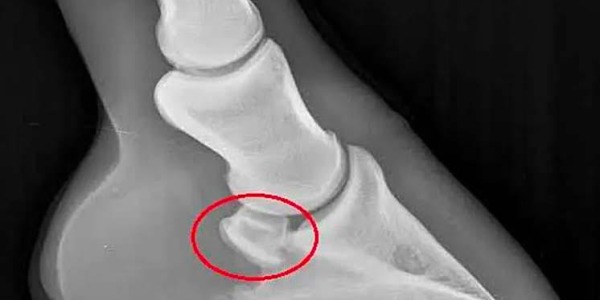

Syndrome Naviculaire : Diagnostic, Signes Cliniques et Traitements pour la Santé Équine